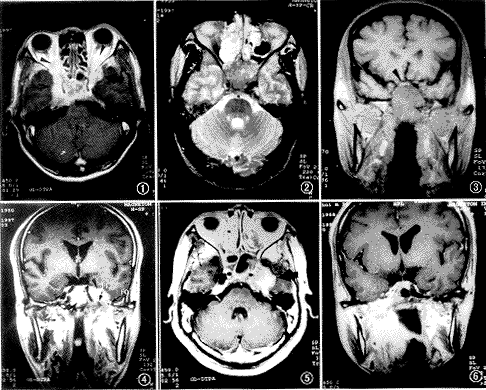

图1 男,47岁。放射治疗(简称放疗)前检查。增强轴位T1WI示双侧海绵窦肿块,向前侵犯双侧眶尖和球后(三角箭头示), 左侧视神经受压,右侧视神经受侵犯

图2 男,42岁。放疗前检查。T2WI示鞍区及后组筛窦软组织肿块,向上侵犯双侧眶尖部,前组筛窦积液

图3 与图2同一病例。冠状面T1WI示鼻咽顶壁肿块,向上侵犯蝶窦和蝶鞍,箭头所示为上抬的视交叉

图4 男,46岁。放疗后2年。增强冠状面T1WI示破裂孔(FL)和卵圆孔(FO)同时受侵犯。左侧海绵窦肿块(▲),蝶窦积液(↑)

图5 与图4同一病例。增强轴位T1WI示左侧海绵窦巨大肿块,左侧颞骨岩尖部受侵犯

图6 男,34岁。放疗后1年半。增强冠状面T1WI示鼻咽右侧壁肿块,侵犯右茎突前间隙,蝶骨体、蝶骨大翼破坏,并经右破裂孔、右卵圆孔侵犯右海绵窦